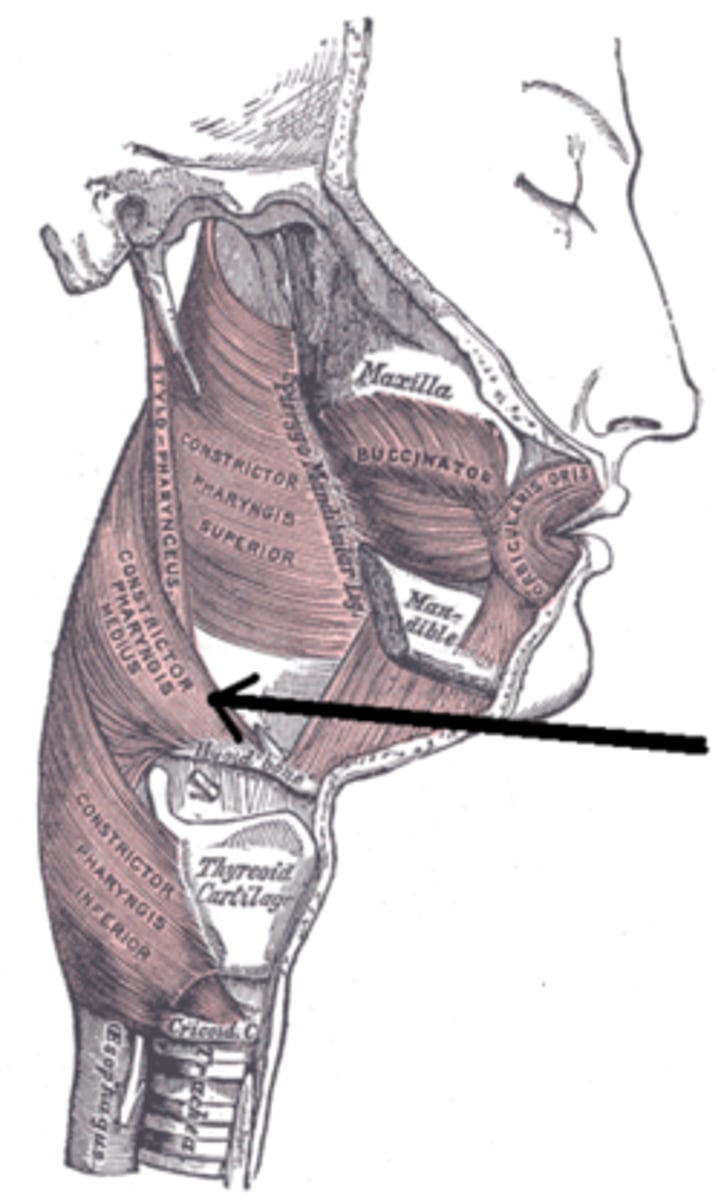

Superior Constrictor Figure

Superior Constrictor Description

Weakest, but most complex of the three

Forms nasopharyngeal and upper

oropharyngeal walls

Origin - sphenoid, mandible, pterygomandibular ligament

Course - posterior, then medial

Insertion - midline raphe

Action - may contribute to velopharyngeal closure by moving posterior wall of pharynx

anteriorly